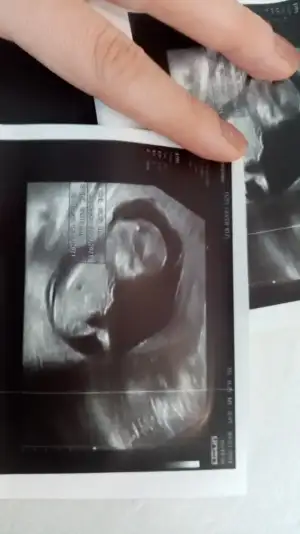

Doktor yuzde yuz kuz demedı ana nubtan anlayanlar yınede bakabılırmı🥰

Eklentiler

• IMG-20210309-WA0009.webp

IMG-20210309-WA0009.webp

17,5 KB · Görüntüleme: 77